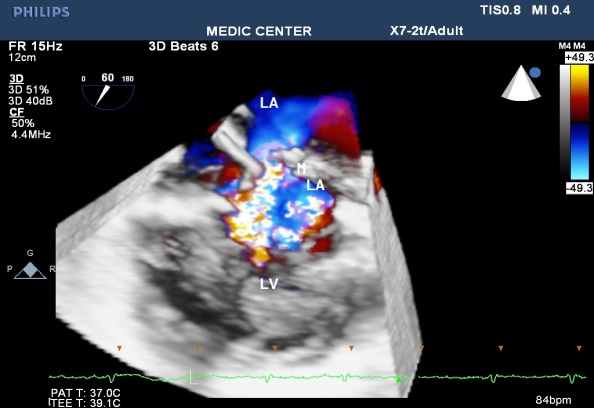

Figure 48. 2DTEE image with details of Cor Triatriatum

Figure 49. Live 3DTEE image showing Cor Triatriatum

Figure 50. Cor Triatriatum with aliasing flow through the separated membrane

Figure 51. Cor Triatriatum viewed from LA . a small opening of membrane noted